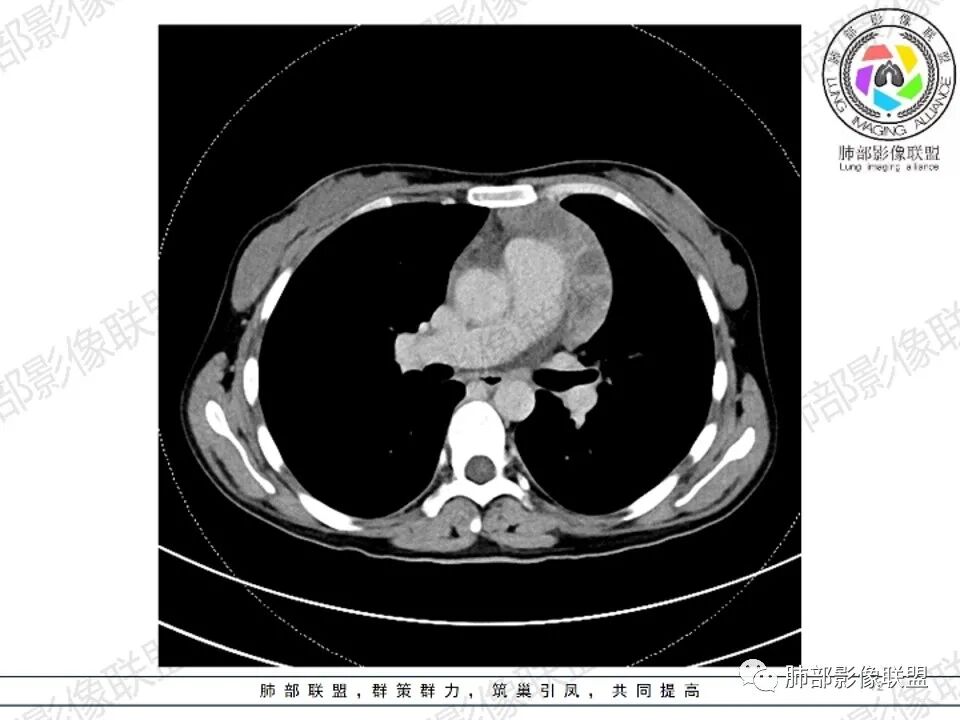

女,27,间断头晕、乏力3年,左眼视物模糊2月。贫血。胸部CT:前纵隔不规则肿块,多结节融合,边界不清,沿主动脉及肺动脉间隙生长,平扫密度欠均匀,增强扫描可见多发低密度坏死,纵隔血管供血穿行,腋窝多发大小不等淋巴结肿大。考虑恶性病变,胸腺癌?肉瘤?淋巴瘤?鉴别胸腺瘤、结节病等。

临床:年轻女性,慢性病程,多系统病变,头晕,贫血,视物模糊。

CT:定位纵膈病变,前中纵隔多发肿块,质软,塑形,密度不均匀,边界清楚。增强不均匀强化,坏死边界清楚,血管漂浮征。双侧腋下多组淋巴结肿大,明显异常强化。

考虑淋巴瘤可能。

2.影像显示前纵隔不规则块状影,依势贴附心脏大血管旁,密度不均,边界不甚清楚,有结节融合感。

3.病灶轻度不均匀强化,可见血管穿行,散在液性低密度区。

双肺门未见肿大淋巴结。

4.双侧腋窝区见增大淋巴结,边界清楚。